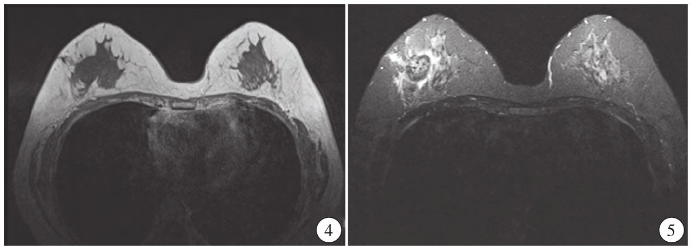

超声检查:右乳腺见大小约3.0cm×1.8 cm×2.4 cm的低回声结节,边界不清,形态不规则,呈角样改变,内见微钙化,弹性成像组织显示蓝色(图1),CDFI显示右乳腺低回声结节内见星点样血流信号(图2);右侧腋窝见约1.4cm×1.1 cm的淋巴结,门结构显示不清,右侧腋窝淋巴结内均见少许星点样血流信号(图3),诊断右乳腺BI-RADS 4c类结节,右侧腋窝异常肿大淋巴结。MRI显示右乳腺外上象限可见结节样稍长T1、稍短T2结节影,边界不清,呈毛刺状,病灶大小约2.1 cm×2.5 cm×2.1 cm,增强扫描呈环形强化(图4、5)。

图1 右乳腺10点处低回声结节,边界不清,形态不规则,呈角样改变,内见微钙化,弹性成像组织显示蓝色。